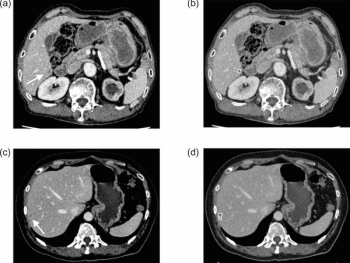

An emerging artificial intelligence (AI) software reportedly detected liver metastases in 53.7 percent of cases involving missed findings by radiologists.